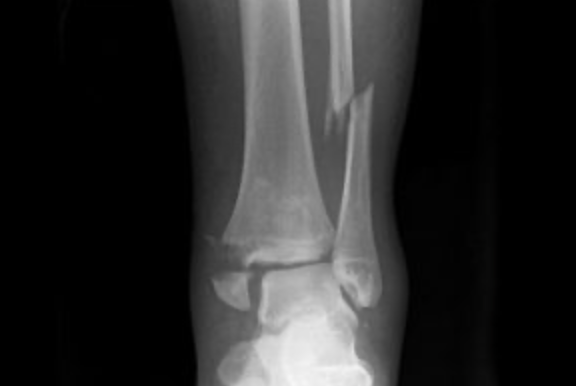

Radiographs demonstrating a disruption of the distal tibiofibular syndesmosis along with a fracture of the proximal fibula, consistent with a Maisonneuve fracture.